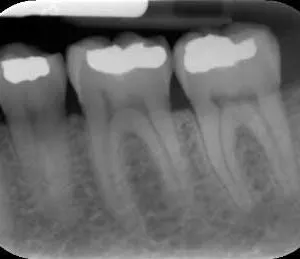

A bite-wing x-ray highlights the crowns of the back teeth. Taken on either one or two sides of the mouth, this x-ray shows the upper and lower molars and bicuspids. In order for these x-rays to be effective, patients are asked to bite down on a wing shaped device, hence the name.

A periapical x-ray looks similar to a bite-wing x-ray. However, it shows the entire length of each tooth, from crown to root.